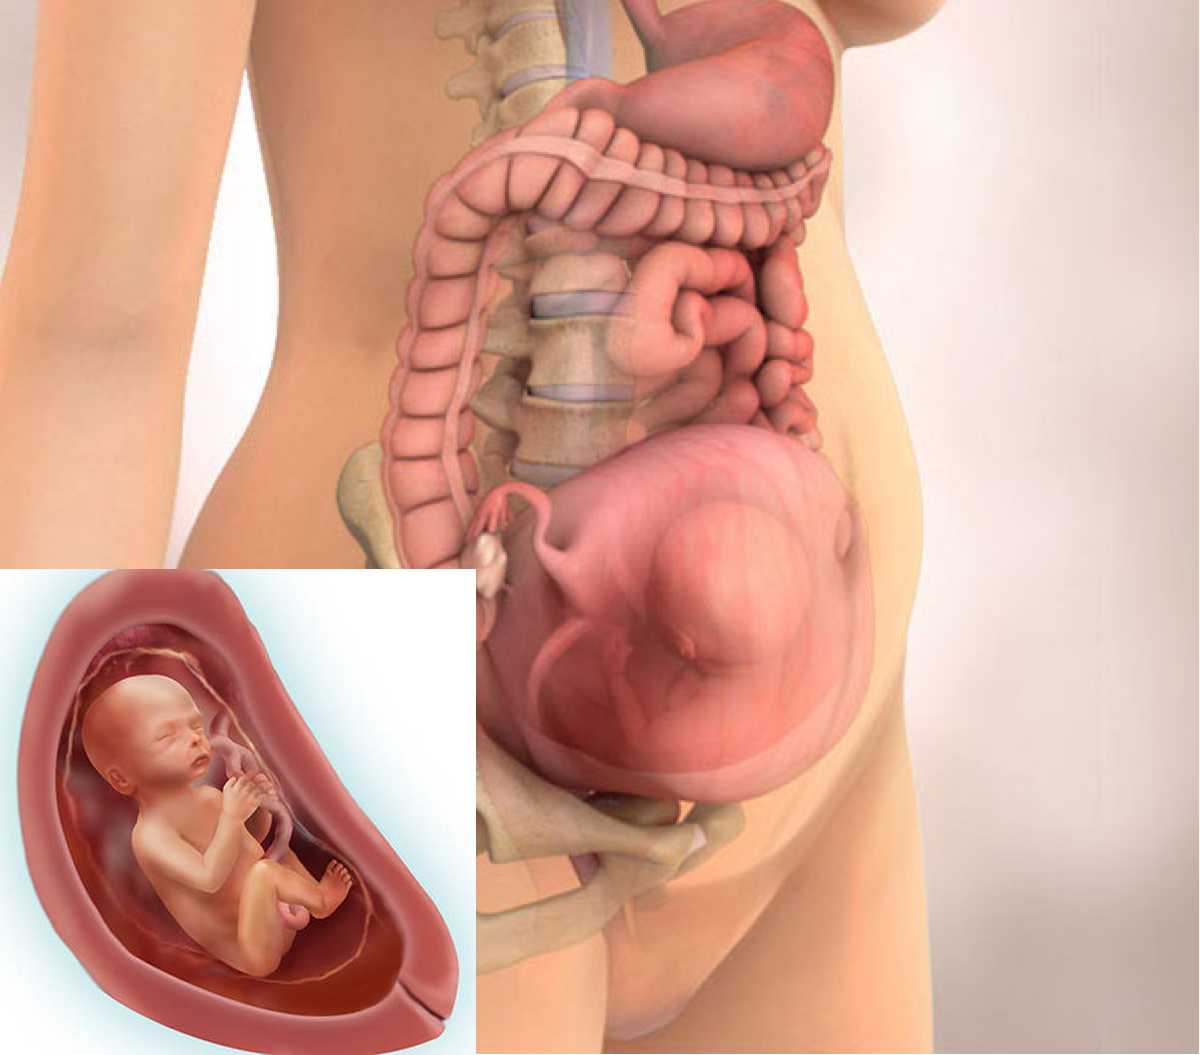

Из-за давления матки на внутренние органы возникают трудности с дыханием. Это проявляется как постоянная нехватка воздуха. К этому нужно привыкнуть, так как устранить данную проблему не получится. Для облегчения состояния нужно чаще бывать на свежем воздухе и регулярно проветривать помещение.

Женщина ощущает, что ее внутренние органы уже изменили свое положение из-за роста матки.

Это могут быть не только чувства давления или растягивания связок и мышц брюшной полости, но и явные симптомы: запоры, связанные с ухудшением перистальтики кишечника, вздутие живота из-за задержки пищи в желудочно-кишечном тракте, быстрое переполнение мочевого пузыря.

Живот на 22 неделе беременности

Живот на 22 неделе вполне заметен. Его форма может немного меняться в зависимости от того, в каком положении находится ребенок. А поворачивается плод в животике довольно часто: у него для этого еще достаточно места. Увеличивается не только живот, но и молочные железы, и отложения подкожной жировой клетчатки на бедрах.

Вес ребенка составляет около 680-700 граммов, а рост порядка 22 см. Малыш активно обрастает жирком, идет развитие его костной и мышечной ткани, совершенствуются внутренние органы.

Пока малыш находится в животике у мамы, он получает кислород через плаценту. Но к моменту рождения его легкие должны быть готовы к самостоятельному дыханию. Поэтому, уже с этого срока начинает вырабатываться вещество под названием сурфактант, которое позволяет держать легкие расправленными, не допускает их склеивание.

К моменту рождения этого вещества уже успевает накопиться столько, что ребенок без труда сделает свой первый вздох самостоятельно. Но это будет ближе к 36-40 неделям. А пока легкие не зрелые. И если малыш родится на этом сроке, то самостоятельно дышать не сможет.

Если у женщины есть угроза прерывания беременности, например, шейка слишком укоротилась, ей в качестве профилактики делают инъекции дексаметазона — препарата, который ускоряет созревание легочной ткани. Таким образом значительно повышается жизнеспособность ребенка и вероятность того, что он сможет самостоятельно дышать после рождения. Если же дексаметазон уколоть не успели, после родов малышу вводят искусственный сурфактант.

На этом сроке уже проводят допплерометрию — то есть смотрят состояние кровотоков ребенка. Если есть нарушения — может потребоваться стационарное лечение. Иногда нарушения бывают критическими, и тогда определяется значительная задержка развития плода, гипоксия. Обычно симптомом этого является медленный рост обхвата живота и высоты дна матки, а также слабые и редкие шевеления ребенка.

Если показания допплера нормальные, плод развивается согласно своему гестационному возрасту, прогноз на течение беременности и родов благоприятный.

При допплерометрии оценивается кровоток в артериях пуповины. Эти показания являются важнейшими характеризующими маточно-плодово-плацентарного кровообращения.

Кроме допплерометрии, на УЗИ в двадцать две недели гестации смотрят структуру плаценты. Она должна иметь однородную структуру. Возможно небольшое расширение межворсинчатых пространств. Данная особенность характерна для женщин, у которых часто бывает пониженным артериальное давление. Степень зрелости плаценты пока нулевая. Если врач ставит уже первую, это означает, что есть риск развития фетоплацентарной недостаточности, внутриутробной задержки развития плода. И, возможно, потребуется сделать перед третьим скрининговым УЗИ еще одно, контрольное, чтобы оценить кровотоки плода.